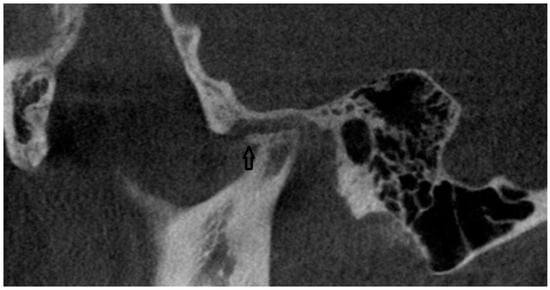

In the CBCT analysis, a comprehensive assessment was conducted on the morphology of the condylar process. This evaluation adhered to established diagnostic criteria aimed at identifying various pathological changes. Specifically, the analysis included the detection and characterization of osteophytes or erosions, indicating localized bone loss or damage, and the presence of cystic formations was evaluated (Figure 1). The study involved a detailed examination of the bone structure itself. This included assessing regions for possible rarefaction or densification. The evaluation extended to the measurement of the joint space width. The condylar fossa and the articular tubercle were also assessed. All CBCT examinations were performed in layers 0.2 mm thick, with 90 kV and 40 mAs using a Carestream CS 9300 (Kodak Dental Systems, San Francisco, CA, USA).

Figure 1. CBCT scan (black arrow points to osteophyte).